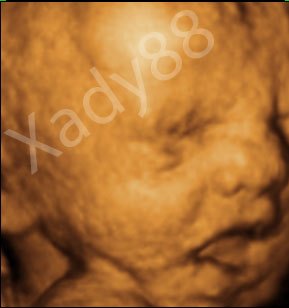

Her er mor og fars lille prinsesse

De to første er fra MD, hvor jeg var 20+